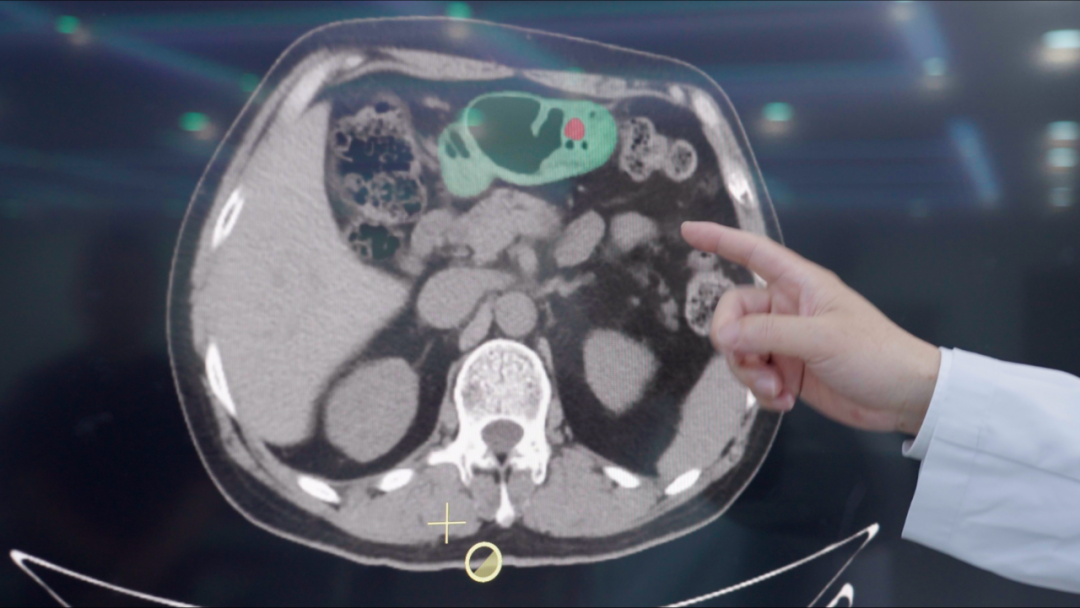

现在医生怎么用这个AI呢?实际工作中,AI会先对腹部平扫CT做初筛,标记出可疑区域,然后医生再对这些高风险人群做胃镜确诊。这样既能提高效率,又不会漏诊。